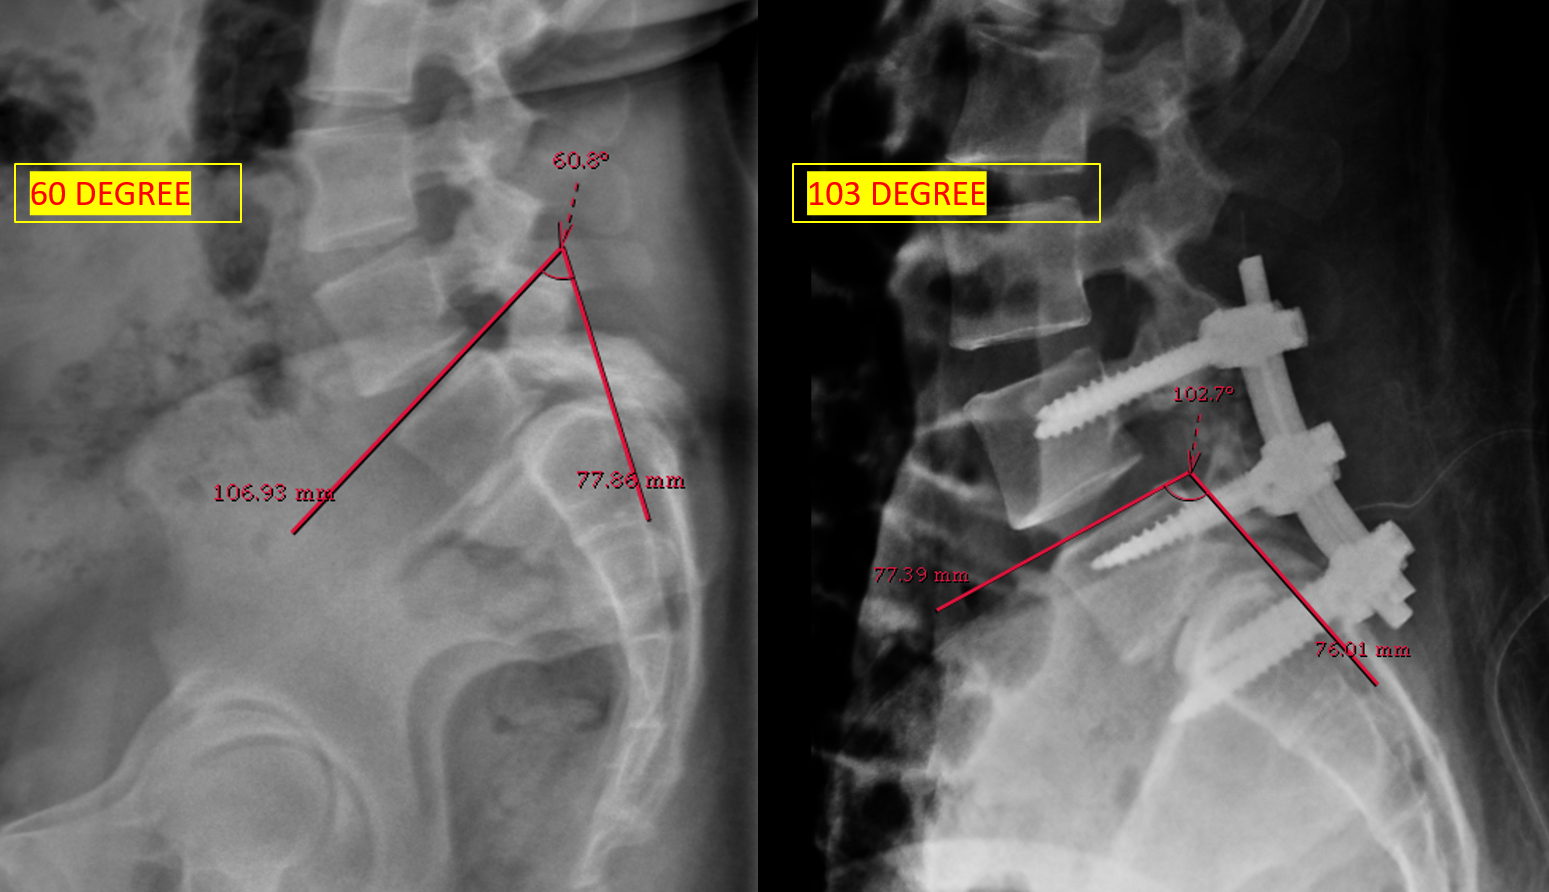

The patient had lumbar spine tenderness localized over the L4 and L5 vertebral levels. Lumbar spine range of motion (ROM) is painful on flexion and extension. Neurological examination showed positive Lasegue’s test at 40° on the right and 30° on left. Motor examination (5/5) in L1, L2, and L3 myotome bilaterally, with reduced power (4/5) in the L4, L5, and S1 myotome on both sides. Sensory examination showed normal sensation in the L1, L2, and L3 dermatomes, reduced sensation on the left at L4, and reduced sensation bilaterally at L5 and S1 S2 S3 S4 S5. Reflex examination showed diminished knee and ankle reflexes and plantar was mute on both side. MRI of lumbar spine with whole spine screening showed anterior listhesis of L5 over S1,central disc bulge,hypertrophy of the facet joints and ligamentum flavum caused severe central canal stenosis, lateral recess narrowing, compression of cauda equina roots, and severe bilateral foraminal stenosis with impingement of the exiting L4 nerve roots bilaterally (Figure1). Post-void residual urine volume is 232 cc on ultrasonography. Diagnosis was high dysplastic spondylolisthesis of L5 over S1, Meyerding Grade III, SDSG – Type 5 balance spine retroverted pelvics based on pelvic incidence 70o pelvic tilt 38osacral slope 32o (Figure 2). The high dysplastic according to the severity index.The patient was counseled on the need for immediate surgical decompression and lumbosacral stabilization to stop neurological deterioration. The recovery of bladder and bowel function was explained to be guarded due to the chronicity of symptoms. After getting informed and written consent the patient underwent posterior decompression and spondylolisthesis reduction with stabilization from L4 to S1, along with bilateral posterolateral fusion at L4-L5-S1 and posterior interbody fusion at L5-S1 under general anesthesia.We fixed L4 also, as the current case is an unstable zone.This zone was identified using a standing lateral radiograph of the lumbar spine that also captures the hips.On radiograph, square area is demarcated by drawing a horizontal line through the center of the S2 vertebral body. The boundaries of the line segment are determined by two vertical reference lines: one is the gravity line, which runs vertically through the midpoint of the inferior endplate of L5, and the other represents the ground reaction force, passing vertically through the center of the femoral head (Figure 3).

Surgical planning was done in the current study, as per the model described by Lamartina. That model provides practical tool for preoperative planning and supports the surgical decision to extend fixation above the L5–S1 segment.8post op lumbosacral kyphosis improved (Figure 4)

Figure 3